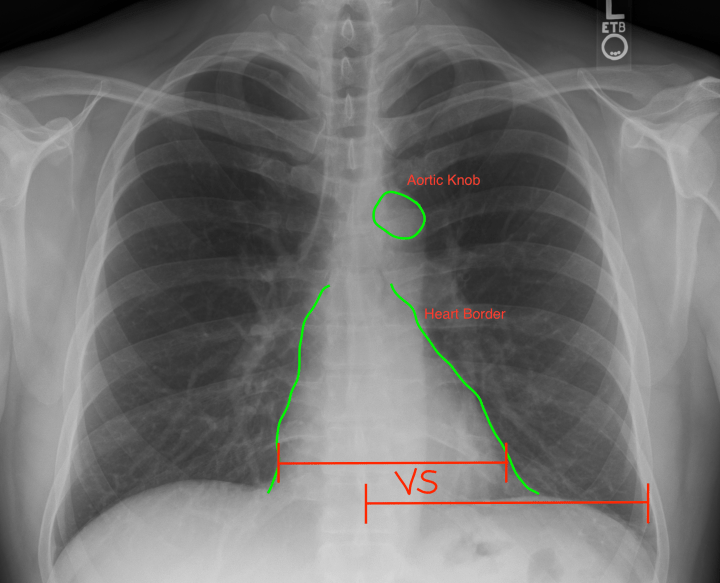

- Cardiac: the 3 C’s: The heart should take up <1/2 the width of the chest. Use your thumb & pointer finger to make a ghetto caliper and compare the heart at its widest point to the distance between the ribs & spinous process. If the heart’s width is greater, the patient presumptively has cardiomegaly. (It’s critical however that you’ve already determined that the patient was not rotated when the CXR was taken. Rotation will produce a falsely narrowed chest diameter AND falsely increased heart width, producing pseudocardiomegaly) Second, the heart should have a clear L & R border that is non obstructed by any lung markings. Patient’s with pneumonia or other lung diseases will have opacities making the border hard to discern. This is not just a “cardiac” check, but also lungs. Lastly, a clear aortic knob should be identifiable. I would dictate this as “heart of appropriate size. no evidence of cardiomegaly. aortic knob observed. clear right & left borders to the heart visualized”.